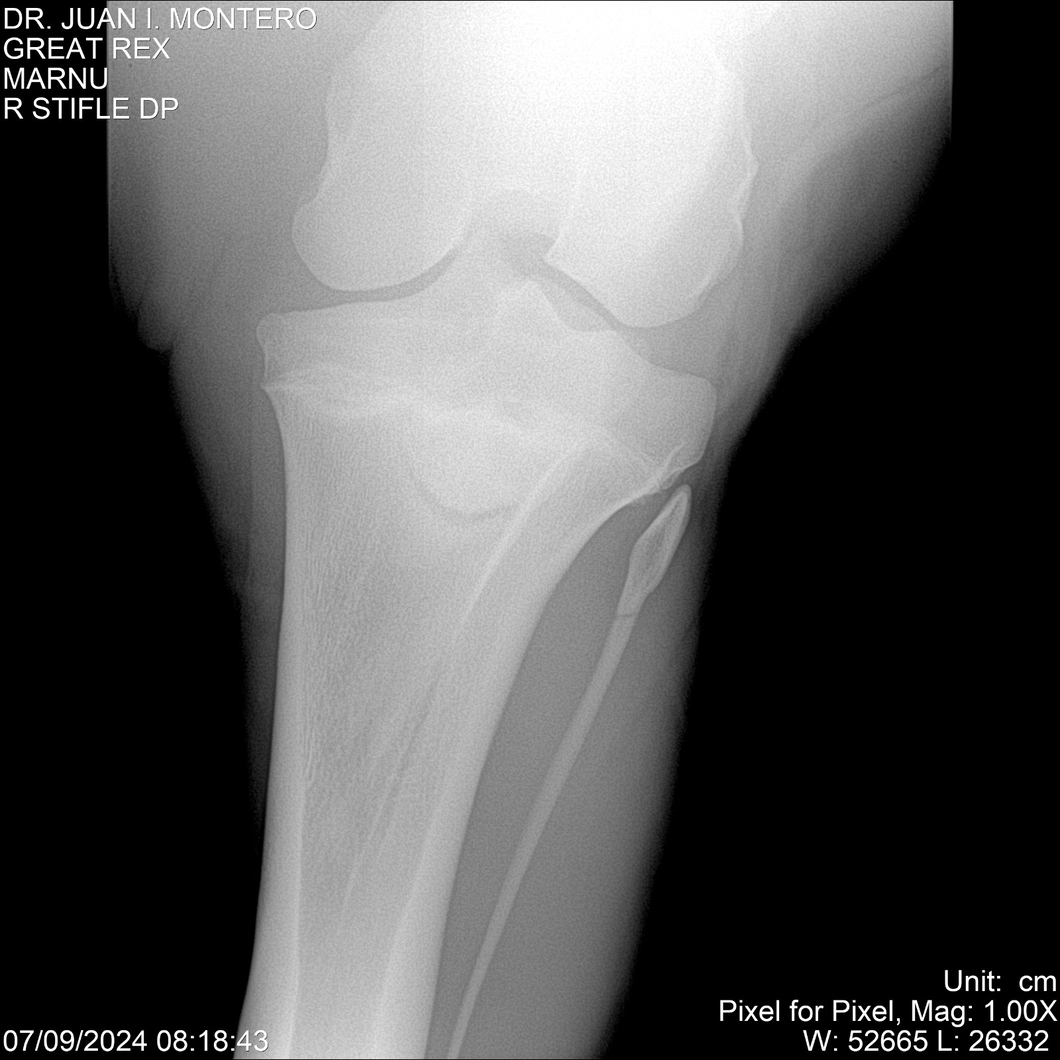

LOTE 4, GREAT REX Lote Anterior Volver al remate Lote Siguiente Ficha Contacto Montevideo - Ficha del Lote Identificador: #282518 Categoría: Yeguarizos Montevideo - 66 Visualizaciones ClicData Contacto Empresa: Abelenda N. R., Walter Hugo Nombre*: Teléfono* : E-mail* : Mensaje Enviar Registrese gratis Este contenido Exclusivo está disponible sólo para usuarios registrados Ingresar